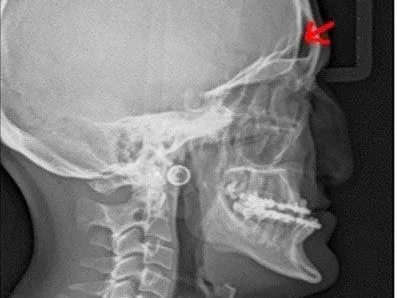

- Globo ocular desplazado hacia adelante (proptosis): es la protrusión o desplazamiento del globo ocular.

- Ojos más separados de lo normal (hipertelorismo): la distancia entre los dos ojos es mayor de lo normal.

- Raíz nasal deprimida: Todos estos problemas anatómicos y estructurales llevan consigo muchos inconvenientes en cuanto al funcionamiento de los sistemas que componen el organismo, en este síndrome se dan sobre todo problemas cardiovasculares anomalías en el sistema genito-urinario, presión intracraneal que condicionara al grado de retraso que pueda sufrir el paciente , disminución de la capacidad auditiva problemas de visión, alteraciones del lenguaje, etc.